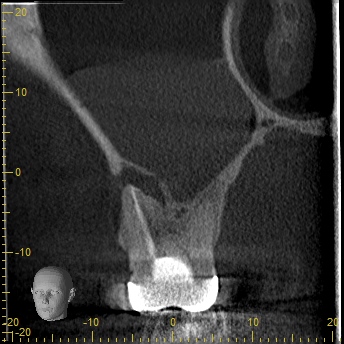

術前CT